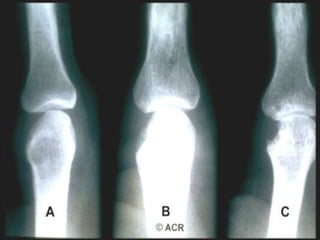

IMAGING

Radiografia: gold standard per la valutazione del danno erosivo;

particolarmente utile per il followup della malattia, per definirne la severità in

un determinato momento e determinare l’efficacia della terapia (follow-up

annuale o addirittura semestrale).

>metodo di Larsen e metodo di Sharp

Erosioni articolari

• L’ Rx convenzionale rappresenta il mezzo più diffuso, rapido

ed economico per evidenziare le erosioni articolari; in realtà

tale tecnica non ne consente, in molti casi, una

individuazione precoce

• Viene quindi ribadita l’importanza dello strumento ecografico

e in particolare dell’eco power-doppler, in quanto mezzo

certamente più economico della RM e più efficace dell’ Rx

convenzionale per evidenziare precocemente le erosioni e la

attività infiammatoria del panno sinoviale

• tutte le metodiche diagnostiche sono comunque utili, ma

l’ecografia è più sensibile

• La presenza di erosioni (a prescindere dalla tecnica

impiegata per la diagnosi) è un importante indice di

aggressività